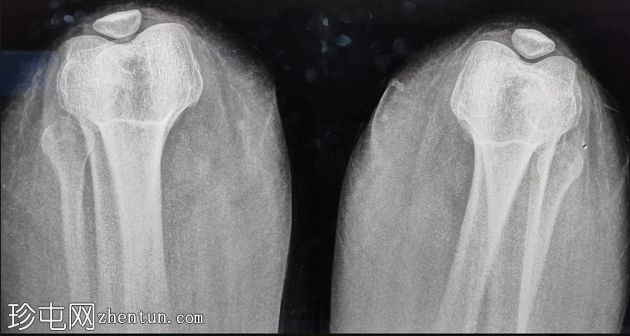

髌骨发育不全

双侧膝关节疼痛

X线片

髌骨相对于股骨滑车发育不良,但形状和结构正常。

其他方面正常。髌股关节间隙正常。未见骨折、碎裂、二分型或软骨损伤迹象。髌骨切线位片未见明显的滑车发育不良或倾斜。

髌骨切线位片清晰显示髌骨相对于股骨滑车的大小。